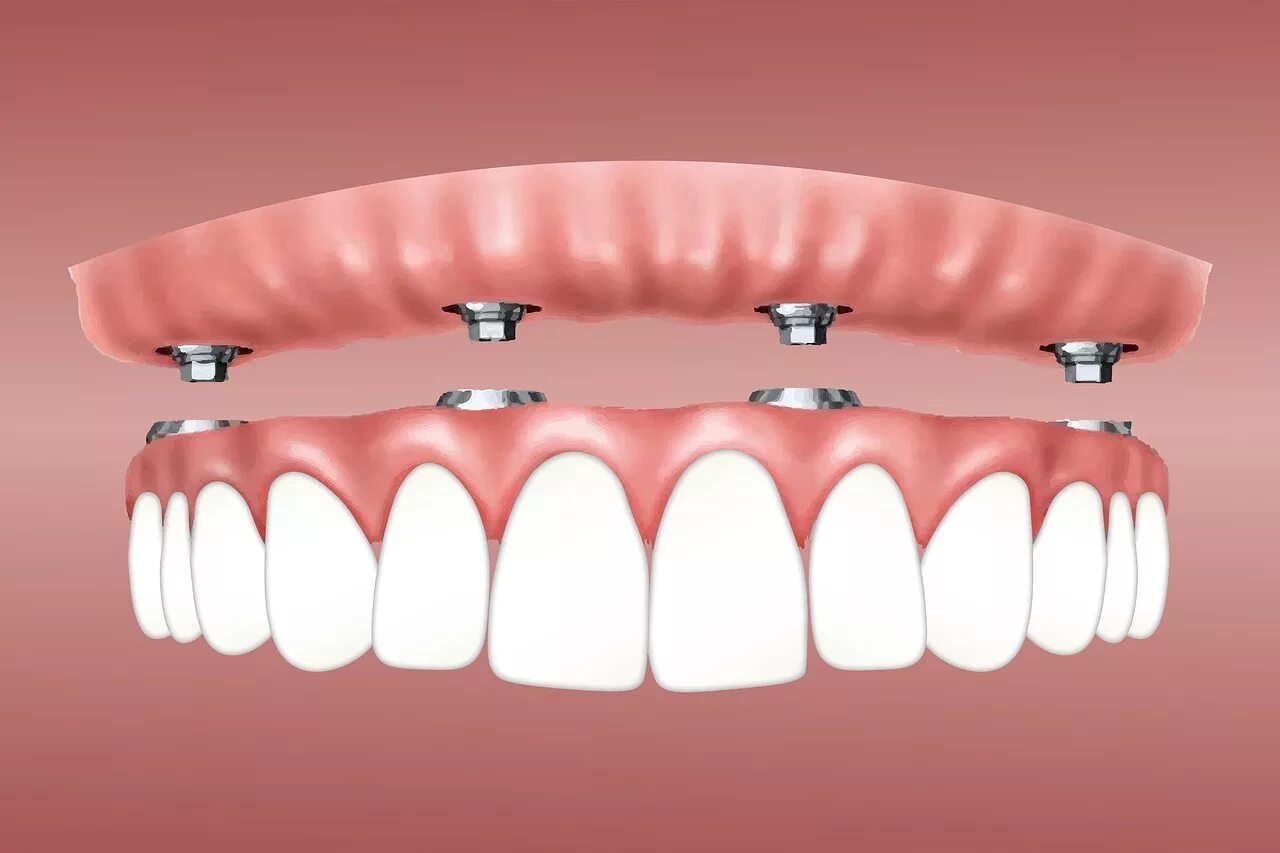

Ол он 4